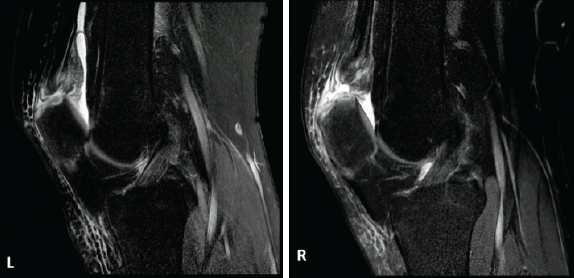

Magnet resonance imaging confirmed in sagittal T2-weighted sequences bilateral total distal quadriceps tendon rupture at the patella insertion site (Fig. 1 and 2). A parathyroid adenoma was diagnosed in axial T2-weighted sequence (Fig. 3).

Figure 1, 2: Magnet resonance imaging of both knees showing complete rupture of both distal quadriceps tendons with proximal retraction.